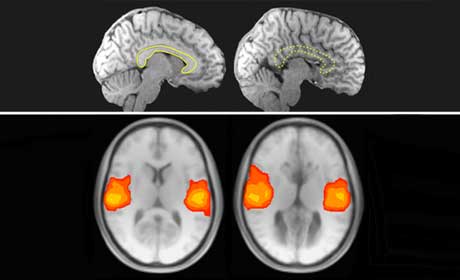

Como un puente que cruza un río para conectar dos grandes metrópolis, el cuerpo calloso es el principal canal para el flujo de información entre los hemisferios derecho e izquierdo de nuestro cerebro. Ahora, los neurocientíficos en el Instituto de Tecnología de California (Caltech) han encontrado que las personas que nacen sin ese vínculo, una condición conocida como agenesia del cuerpo calloso, o AGCC-aún muestran notablementela comunicación normal a través de la brecha entre las dos mitades de su cerebro.Nuestros cerebros no están realmente en reposo. Incluso cuando soñamos despiertos, hay una enorme cantidad de comunicación pasando entre las diferentes áreas en el cerebro. De acuerdo con Michael J. Tyszka, autor principal del Journal of Neuroscience y director asociado del Centro de Caltech imágenes cerebrales, muchas áreas del cerebro muestra que varía lentamente patrones de actividad que son similares entre sí. El hecho de que estas áreas se sincronizan ha llevado a muchos científicos a suponer que todos ellos son parte de una red interconectada llamada de una red de descanso del estado. Para su sorpresa, Tyszka y su equipo encontraron que estas redes de descanso Estado mirada esencialmente normal en las personas con AGCC, a pesar de la falta de conectividad.

El trabajo utiliza la resonancia magnética funcional (fMRI) para demostrar que la actividad sincronizada entre el cerebro izquierdo y derecho perdura incluso este tipo de cableado radical de las conexiones nerviosas entre los dos hemisferios. La presencia de patrones simétricos de la actividad en las personas que nacen sin un cuerpo calloso más destacados notable plasticidad del cerebro y su capacidad para compensar, dice el coautor Lynn Paul, miembro del personal de investigación y profesor de psicología en Caltech. «Se desarrolla estas redes fundamentales, incluso cuando los hemisferios izquierdo y derecho son estructuralmente desconectado.»

El estudio que encontró que las potentes redes es parte de un programa continuo de investigación dirigido por Paul, quien ha estado estudiando AGCC durante varias décadas. AGCC se presenta en aproximadamente uno de cada 4000 nacidos vivos. El cuerpo calloso típico consta de casi 200 millones de axones, las conexiones entre las células del cerebro y es el paquete más grande de fibras en el cerebro humano. En AGCC, esas fibras no cruzar la brecha entre los hemisferios durante el desarrollo fetal, lo que obligó a los dos hemisferios del cerebro para comunicarse con los medios más indirectos y desconocidos en la actualidad.